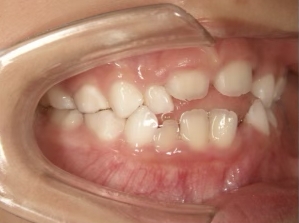

治療中⑥ 小6:11y8m

モノブロック装置継続中、左上八重歯の改善中